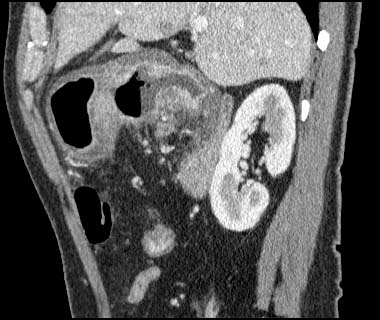

Gastric cancer / Borr.III

1mmx4, Pitch 4.5, 23 seconds, 150mAs

Sagittal MPR

Data acquired & processed by H. Anno M.D.